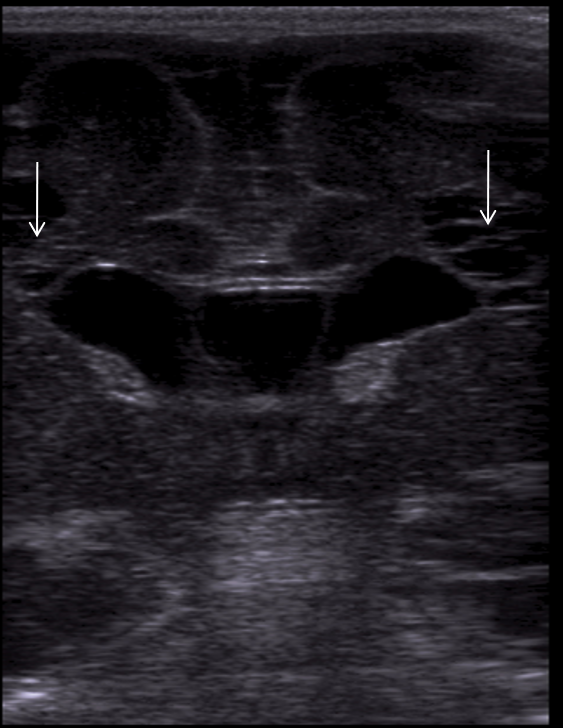

Neonatology Grade 3 PVL 1 Image